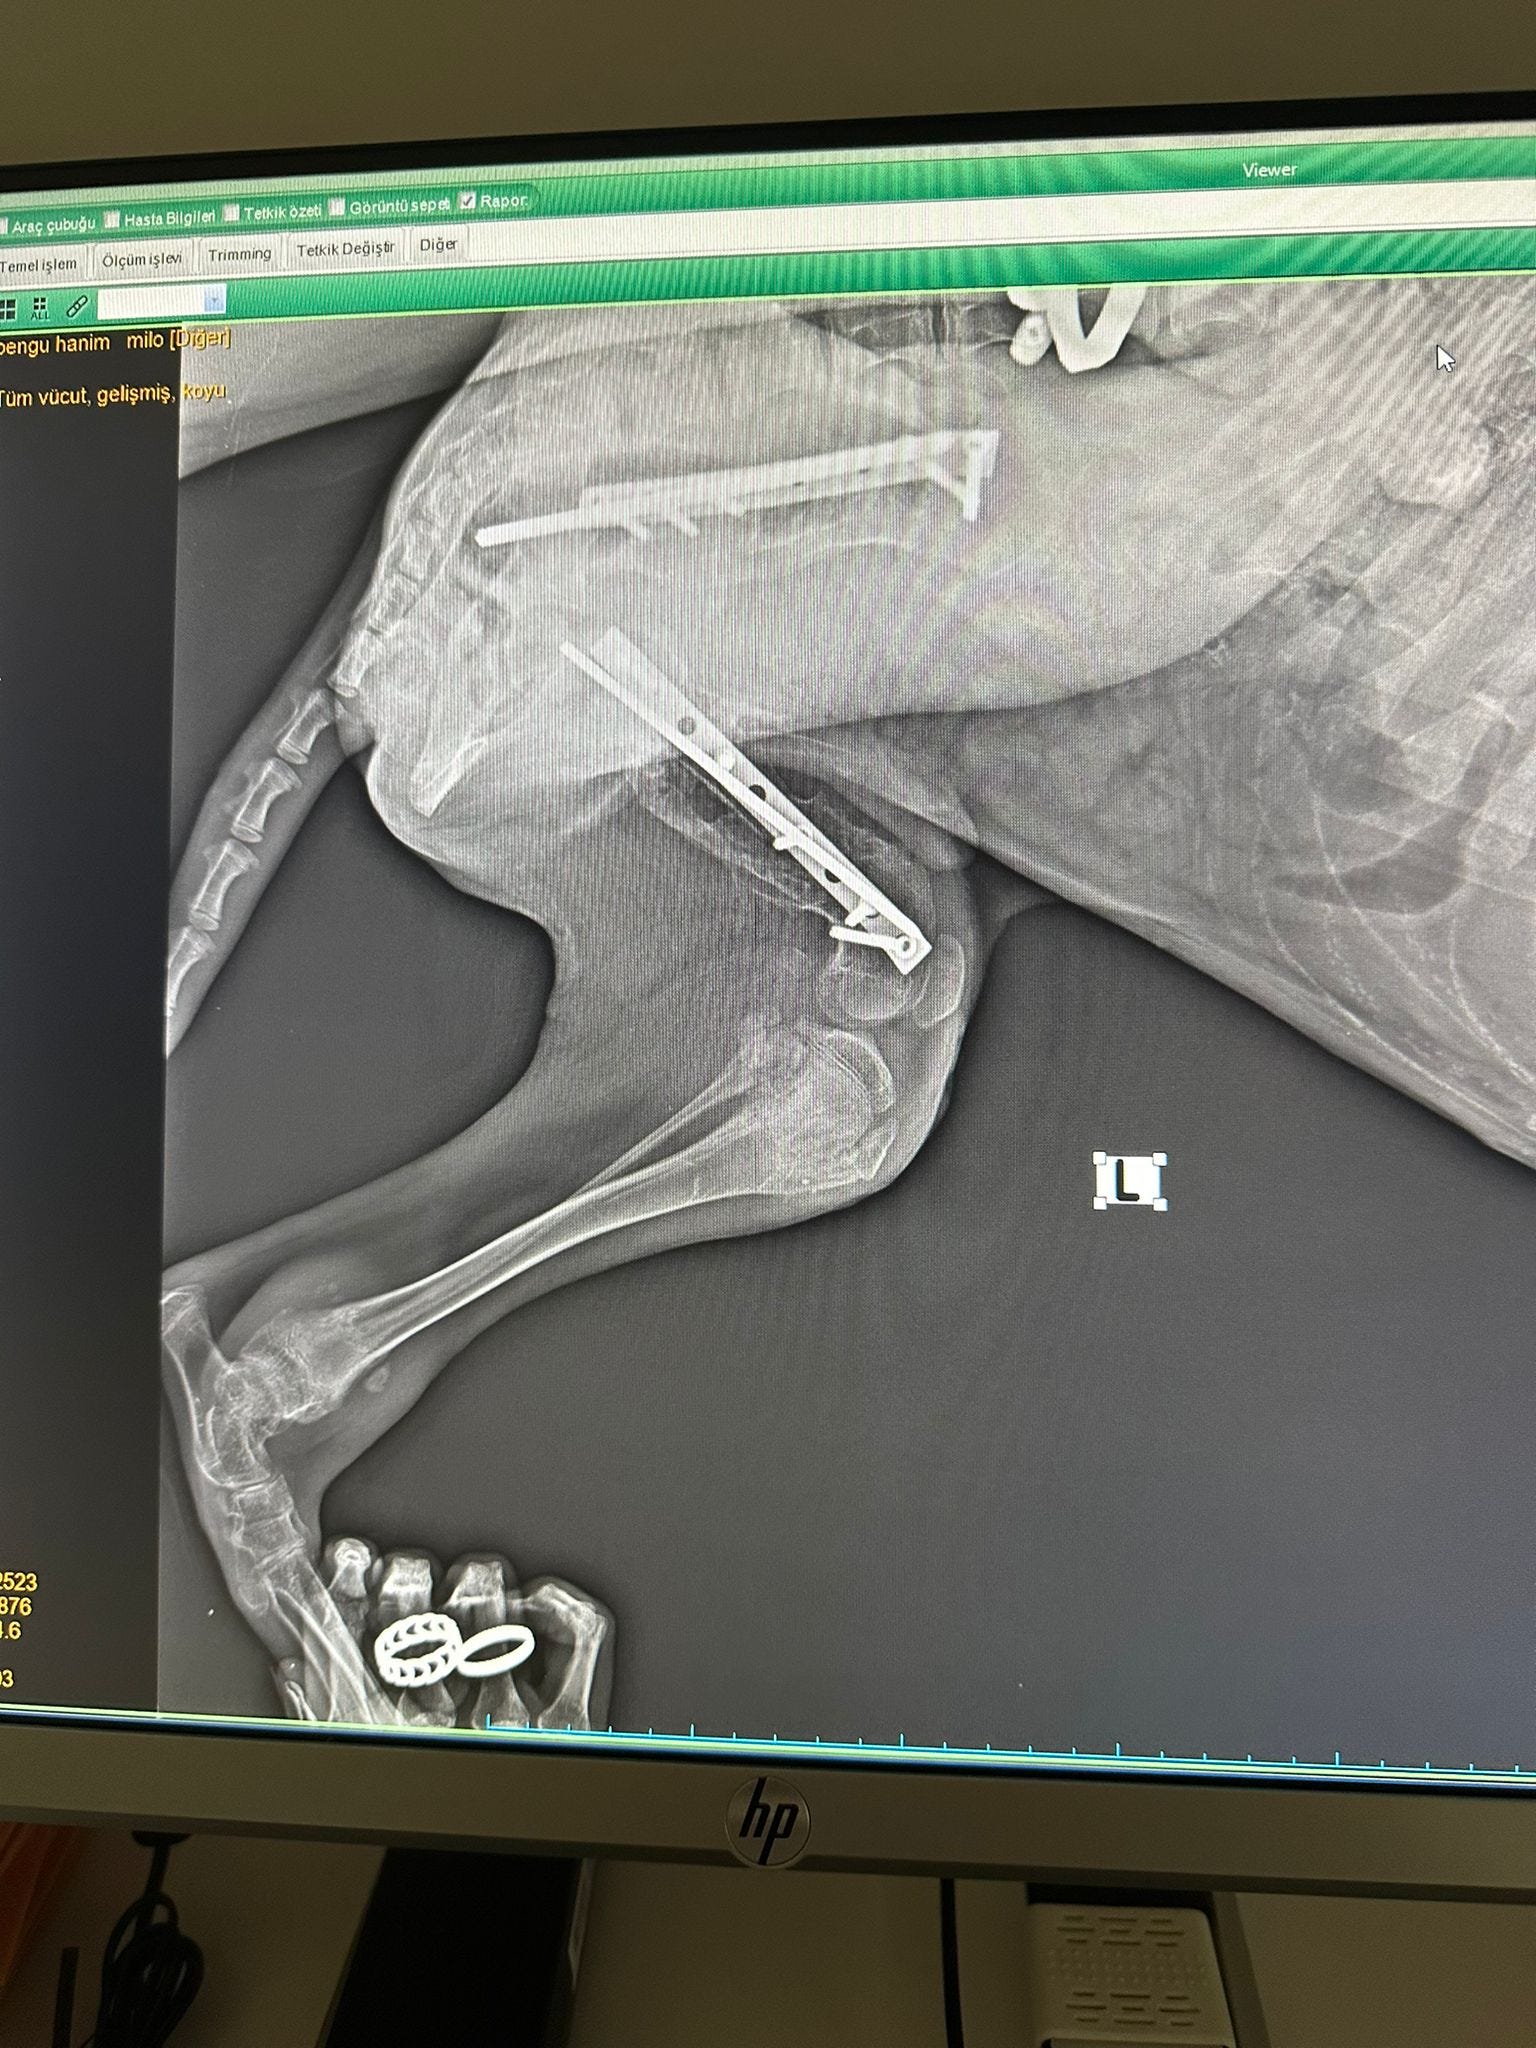

The stiffness in Milo’s leg, which we mentioned earlier, was eventually traced to a failed surgical plate.

Sadly, while not common, plates can sometimes fail, and in Milo’s case it caused further complications. A replacement plate was fitted, but damage to the surrounding muscle from the original procedure meant that his recovery was severely hindered.

For months, Milo struggled to carry the useless limb, which was clearly slowing him down and preventing him from thriving. After much thought and discussion, we made the difficult but compassionate decision to amputate.